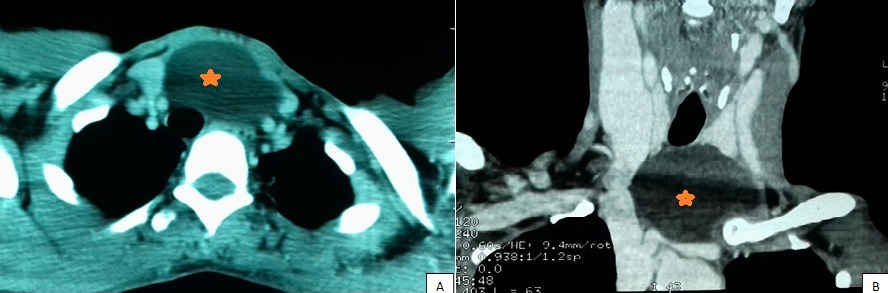

Les kystes thymiques sont des tumeurs congénitales rares, présentant 1% des masses cervicales kystiques de l'enfant. Ces kystes sont extrêmement rares chez l'adulte. Nous rapportons le cas d'une femme âgée de 50 ans, sans antécédents particuliers, qui a consulté pour une tuméfaction basi-cervicale antérieure évoluant progressivement depuis 2 ans avec une dyspnée d'effort. A l'examen, elle présentait une tuméfaction basi-cervicale antérieure faisant 4 * 4cm de diamètre, molle, non mobile à la déglutition. L'échographie cervicale a montré une formation kystique ovalaire sous cutanée du creux sus sternal plongeant au niveau du médiastin de 4 * 2.5 * 3cm de dimensions. Le complément par une TDM cervico-thoracique a montré une masse hypodense cervico-médiastinale médiane venant au contact des troncs supra aortiques, refoulant la thyroïde en haut et se développant en bas vers la loge thymique, mesurant 46 * 64 * 58mm. L'exploration chirurgicale par cervicotomie a trouvé une masse kystique tendue bien encapsulée de la loge thyroïdienne étendue au médiastin antérieur, à contenu jaune citrin. La masse était extirpée complètement par voie cervicale. L'étude histologique de la pièce opératoire était en faveur d'un kyste thymique. Le recul est de 1 an avec une bonne évolution sans récidive. Les kystes thymiques, bien que rares, doivent être évoqués devant toute masse kystique cervicale ou cervico-médiastinale, même de l'adulte. La TDM, l'IRM et la cytoponction préopératoires sont utiles, mais la confirmation diagnostique nécessite l'identification du tissu thymique contenant les corpuscules de Hassall à l'examen anatomopathologique. Le traitement est chirurgical avec une exérèse complète de la paroi kystique afin d'éviter les récidives.